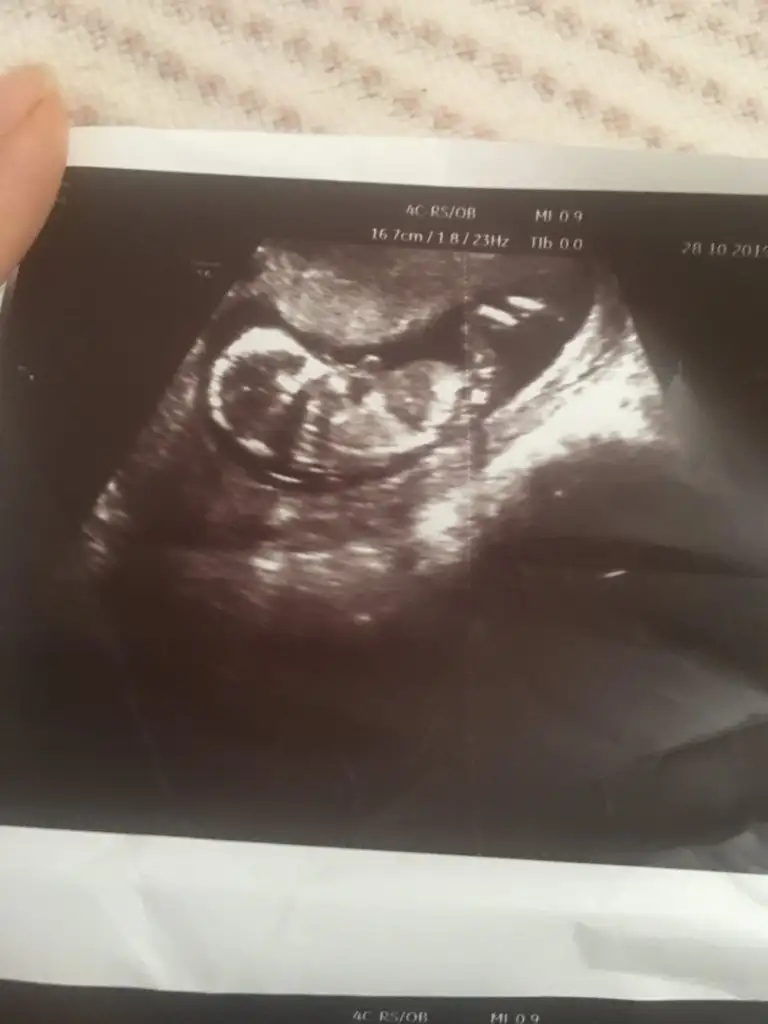

başka usg var yüklüyorum şimdiKız gibi gibi diyorum başka usg varmı

başka usg var yüklüyorum şimdi

Bi tane daha var

Buda net degil cnm 12 hafta usg paylaşırsınBide bunlar var

11 haftalik